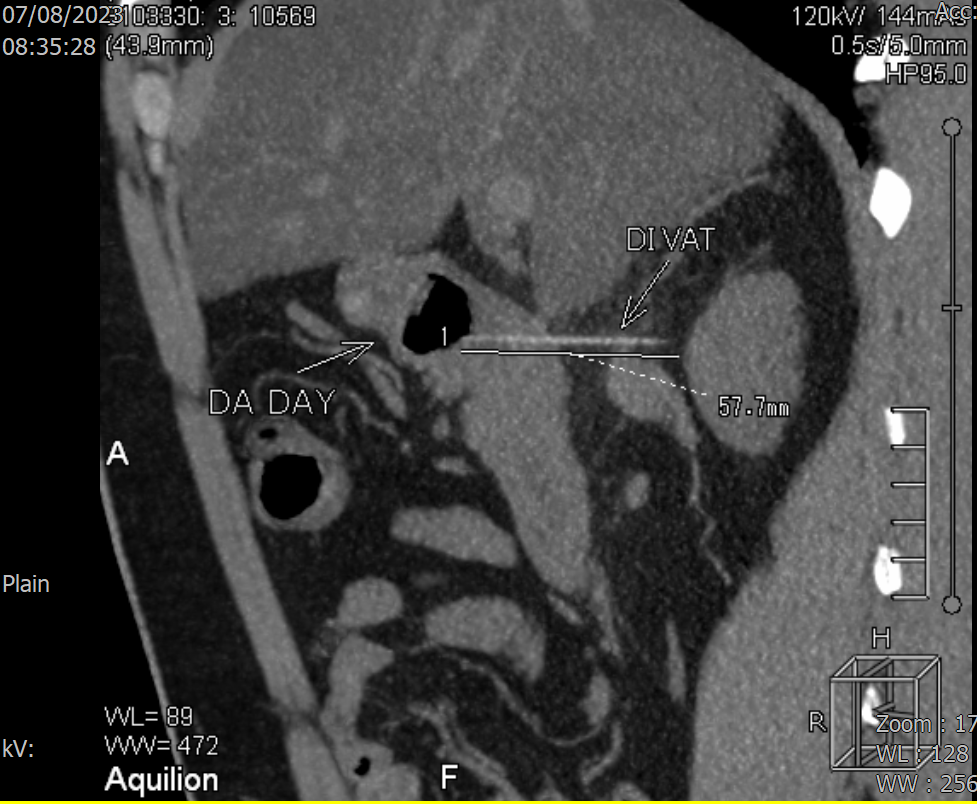

Tại Khoa Cấp cứu, nhận định ông Q. có khả năng bị thủng dạ dày do nuốt phải dị vật, các bác sĩ chỉ định ông Q. thực hiện chụp CT bụng chậu khẩn. Kết quả phát hiện dị vật dạng que thẳng, đường kính 2mm dài 4,5cm xuyên thành mặt sau hành tá tràng vào mô mỡ phúc mạc.